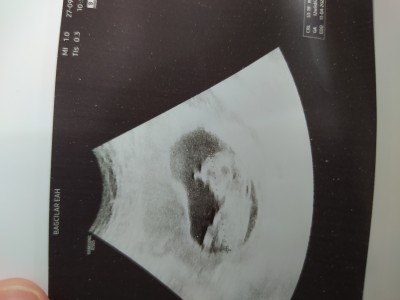

image

19 haftalık burda ve hala emin değil hiç bir doktor

Kız o zaman cnm. Crl baş popo mesafesi. Erkekte az kızda çok oluyor. İki oğlumda 15 nci haftada iken 5 ila 7 mm arasindaydi

İnşallah canm iki oğlum var sezeryan oluyorum kızım olursa nokta koyacam

Crl ile cinsiyetin bir alakası yoktur, doktoruma da sordum. Kimilerinde cm yazar kimilerinde mm. Cm ile mm aynı şeyler değil biliyorsunuzdur. Siz buna dikkat etmeden yorumluyorsunuz galiba. Bir bebeğin 15. haftada baş-popo mesafesinin 5-7 mm olma ihtimali yok, gelişim geriliği vardır yani. 5-7 cm olmasın o ? Benim 5+6'da CRL 3.53 mmdi mesela. Nerdeyse susamken bile 3 mm yani.